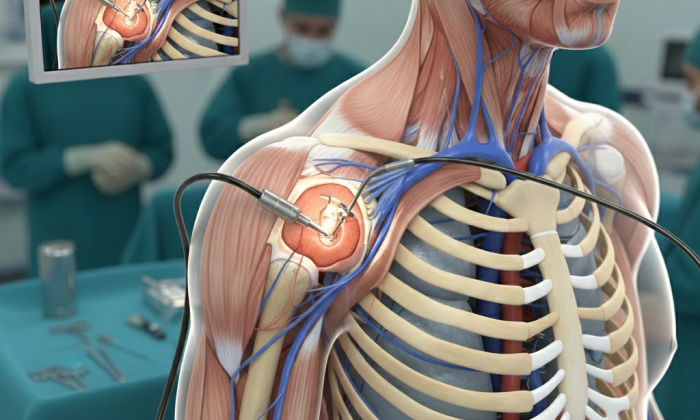

Omuz artroskopisi, eklem içindeki sorunları teşhis ve tedavi etmek için kullanılan minimal invaziv bir cerrahi...